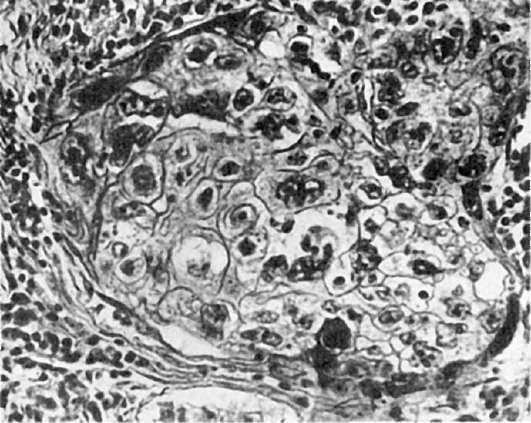

Клеточный атипизм на светооптическом уровне выражается в полиморфизме или, напротив, мономорфизме клеток, ядер и ядрышек, гиперхромии ядер (рис. 96), полиплоидии, изменениях ядерноцитоплазматического индекса в пользу ядер в связи с их укрупнением, появлении множества митозов.

Рис.

96. Клеточный атипизм и полиморфизм опухоли